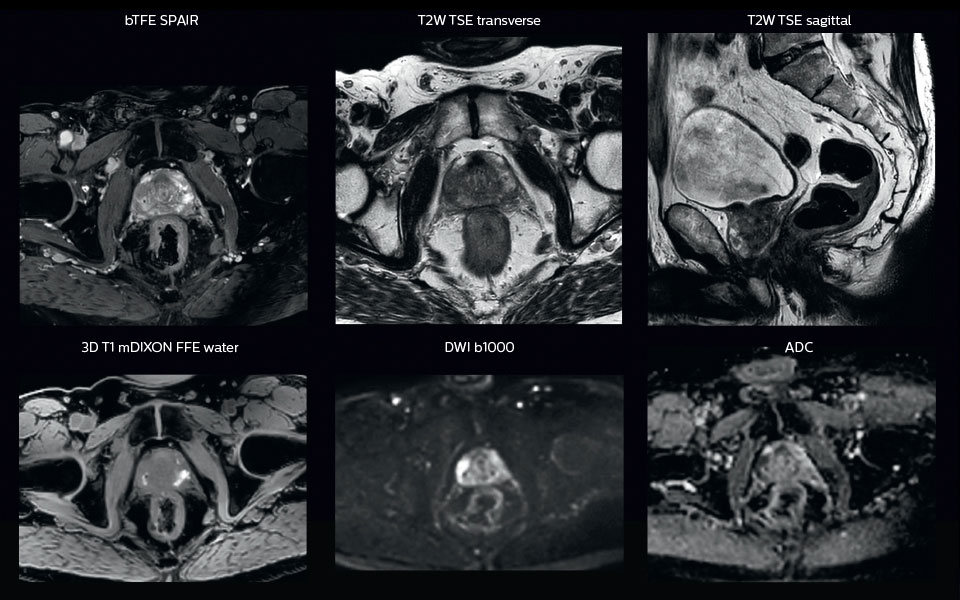

“All our patients undergo an MRI exam – along with CT – before radiotherapy of the prostate,” says Dr. Philippens. “For prostate delineation, we are scanning a balanced TFE with fat suppression. We can also see the gold fiducial markers in these images, which are used for position verification and are therefore used for registration to CT. For geometric accuracy of the image, we choose a 3D sequence, which is corrected for the gradient non-linearities in all directions.

“In addition to helping in delineation of the prostate, MRI also helps in visualizing the lesions inside the prostate, which may not be possible in CT.

“When we can visualize intraprostatic lesions, the radiation therapist can then plan to boost them, giving a higher dose to those lesions instead of giving a uniform dose to the whole prostate, in the hope to better treat the patient and have less risk of recurrent tumors. However, this is not yet clinical routine. For visualizing the lesions, we not only use anatomical, T2-weighted imaging, but also diffusion weighted MRI and dynamic contrast- enhanced MRI."

A 63-year-old patient with prostate cancer, cT3bNxM, Gleason 7, underwent MRI on Ingenia 3.0T MR-RT before radiation therapy.

Intraprostatic lesions are visible on the bTFE MR image, but not on the CT image. MRI shows excellent soft-tissue contrast for the visualization of critical structures like the rectum and penile bulb.

Fiducial markers (green arrows) are used in registration of MR images to CT, to transfer the MR-based delineations onto the CT image dataset.